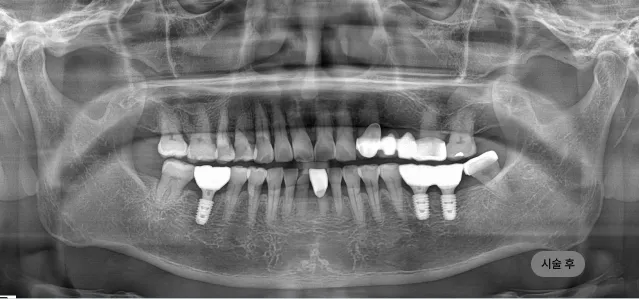

화면을 드래그하여 전/후를 비교해 보세요